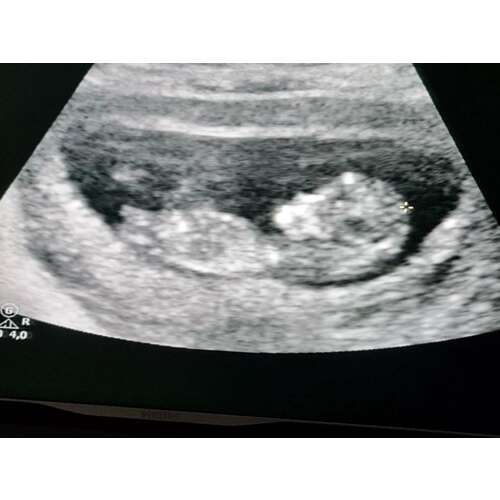

Ben hier 11.5 weken 🙈 ben benieuwd naar jullie reacties 🤩

Op moment nog meisje.maar tot 12 weken kan de nub nog veranderen naar een jongens nub. Sommige jongens zijn wat eerder sommigen wat later. Dus is nog even afwachten of het een meisjes nub blijft